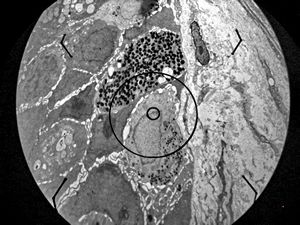

M,54y. | Whipple disease

Whipple disease